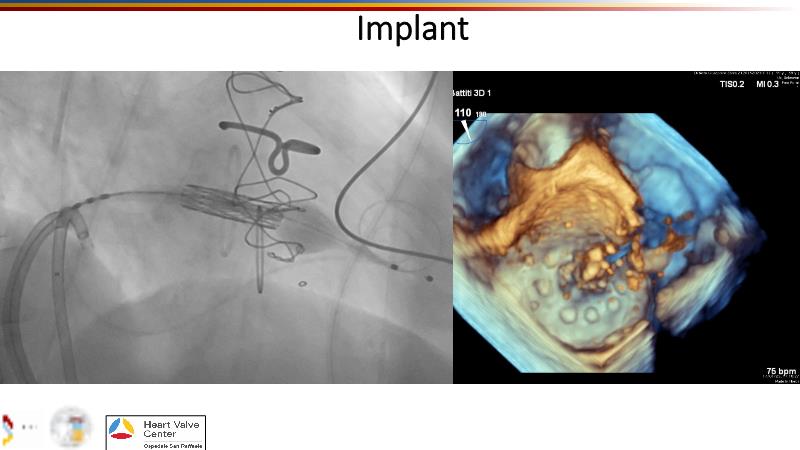

Explore cutting-edge transcatheter valve interventions for mitral and aortic valve disorders, including valve-in-valve procedures and management strategies for paravalvular leakages, and learn about diagnosing and treating mitral annular calcification and transcatheter options in infective endocarditis.

- To get tips and tricks for guidance of transcatheter intervention